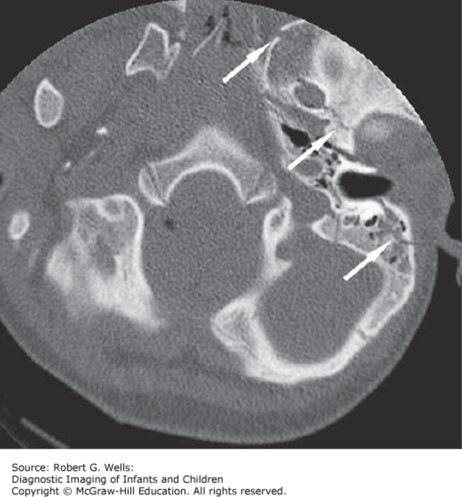

Basilar skull fracture. A longitudinal fracture (arrows) extends through the petrous portion of the left temporal bone, foramen ovale, and greater wing of the sphenoid bone.

Source: Wells RG. Diagnostic Imaging of Infants and Children; 2015.